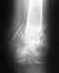

"У мальчика 6 лет в марте этого года был двойной перелом левой ключицы:1) вблизи грудинного конца (соотношение отломков в прямой проекции - удовлетворительное и 2) в средней 1/3 (отломки стоят под тупым углом, открытом книзу). В стационаре сделали операцию, вставили спицу. Спустя почти два месяца гипс сняли, спицу удалили. А через три недели ребенок сломал эту же ключицу снова: в средней трети без смещения. Местный хирург наложил гипс на три недели. В конце первой недели ребенок еще раз упал на больное плечо, после чего был сделан новый рентгеновский снимок, показавший увеличение угла между отломками. Участковый хирург сказал, что угол в пределах допустимого и через еще две недели гипс снял. По своей инициативе мы провели дополнительное обследование сына, в том числе МСКТ, результатом которого стал следующее "...определяется перелом диафиза левой ключицы. Смежные поверхности костных фрагментов уплотнены, костно-мозговой канал облитерирован костной мозолью. Линия перелома определяется на всем протяжении за исключением ограниченных участков в области массивных периостальных наслоений по задней и передней поверхностям. Прилежащие мягкие ткани, дифференцированы, не увеличены в объеме. Заключение: Замедленно срастающийся перелом диафиза левой ключицы с тенденцией формирования ложного сустава." Хирург, у которого уже консультировались, считает, что необходима операция с пластиной. Но, так как операция у ребенка будет уже вторая за полгода, хотелось бы узнать, возможны ли какие-либо иные варианты в нашем случае".

Снимки и МСКТ по ссылкам:

это в день второго перелома

http://foto.mail.ru/inbox/skwo/576/i-594.jpg

это через неделю

http://foto.mail.ru/inbox/skwo/576/i-596.jpg

это пять дней назад

http://foto.mail.ru/inbox/skwo/576/i-593.jpg это МСКТ (23.07)